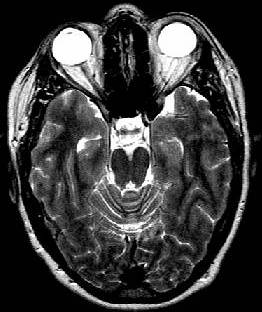

| Substance |

T2 weighted |

| Water/Vitreous/CSF |

Light grey or white |

| Fat |

Light grey |

| Muscle |

Grey |

| Air |

Black |

| Fatty bone marrow |

| Brain: White matter |

| Brain: Grey matter |

very light grey |